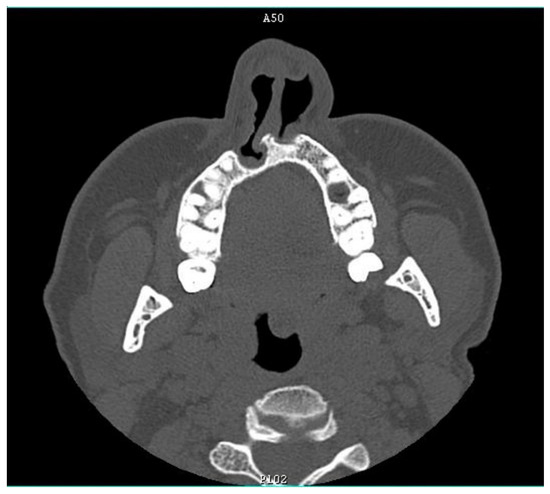

Figure 2). A hand X-ray at the age of 3 years showed four fingers of the right hand with thumb aplasia and a decreased bone age with an incorrect order of wrist bones ossification.